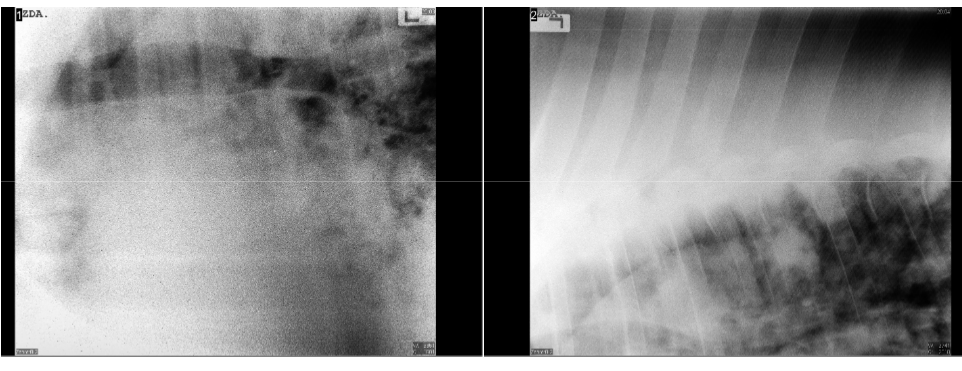

• Radiography can help identify more internal pathology of the lungs. When trying to take images of the lungs attempt to remove fluid from the thorax beforehand to get a more clear image of the lungs.

• what is the diagnosis from this image?

pulmonary abscess